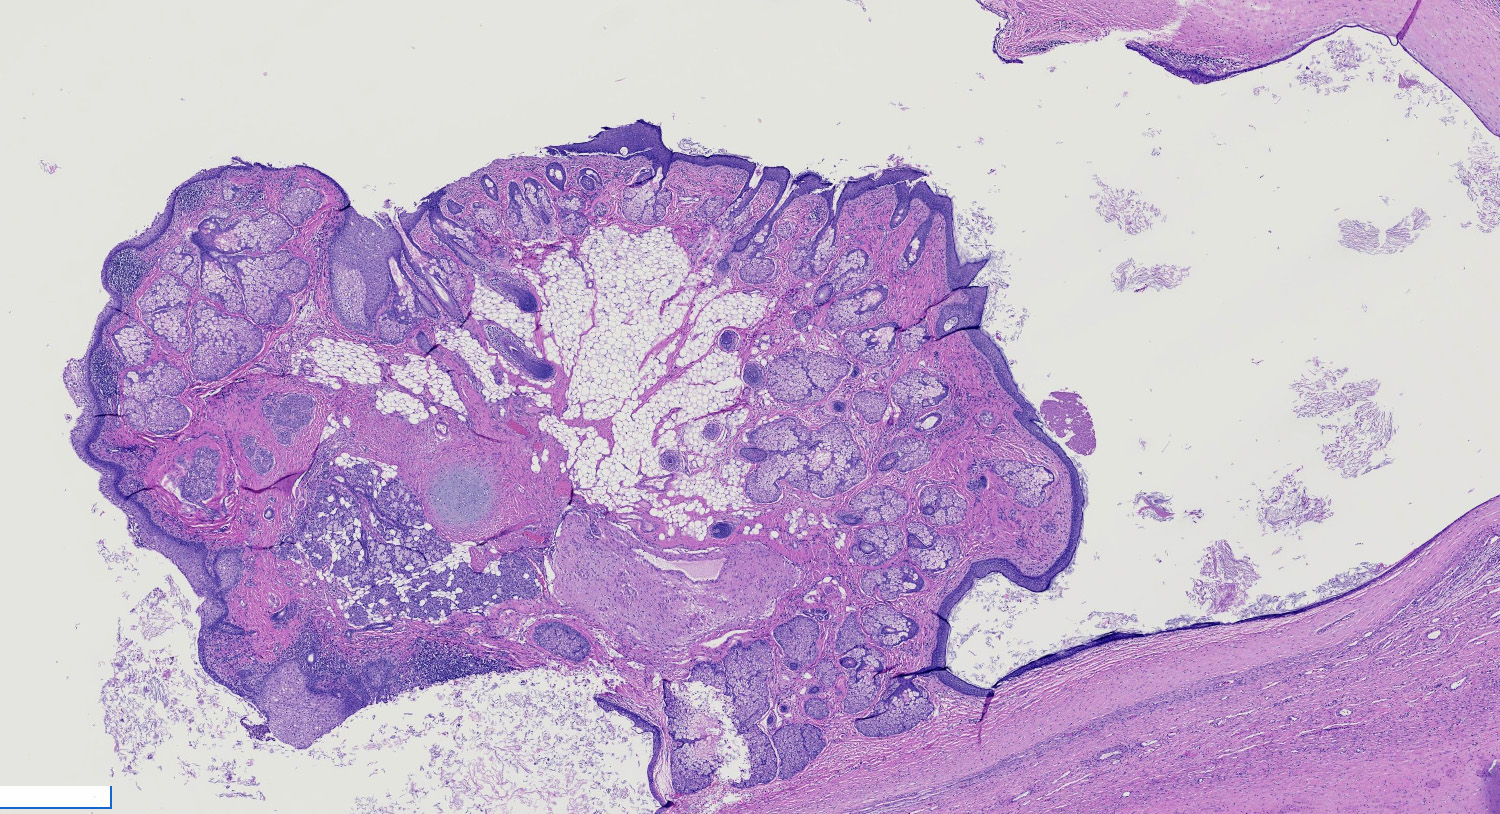

Gross description

- Smooth cyst that may contain hair, teeth, cartilage, bone or sebaceous material

- Generally < 10 cm

- Raised protuberance in cyst wall (Rokitansky nodule)

- Reference: StatPearls: Cystic Teratoma [Accessed 29 July 2021]

Gross images

A 25 year old pregnant woman is seen in the obstetrics clinic for a routine ultrasound. During the exam, a cystic mass is noted near her left ovary. The mass is eventually surgically removed and a pathologic examination shows the features in the picture shown above. What is an essential feature of this tumor?

C. Mature tissue representing at least 2 embryonic layers. Mature teratoma can contain microscopic foci of immature neuroectodermal tissue in the cyst wall. This finding does not change the prognosis and should not lead to the tumor being classified as immature teratoma. Gliomatosis peritonei is a rare finding associated with teratoma and size of tumor is variable with most less than 10 cm. Mature teratomas must contain at least 2 embryonic layers.

D. Mature teratoma. The photo shows a mass with yellow sebaceous material and hair. In a 19 year old woman, this most likely represents a mature teratoma. Mature teratomas are the most common ovarian tumor and are especially common in women of reproductive age.